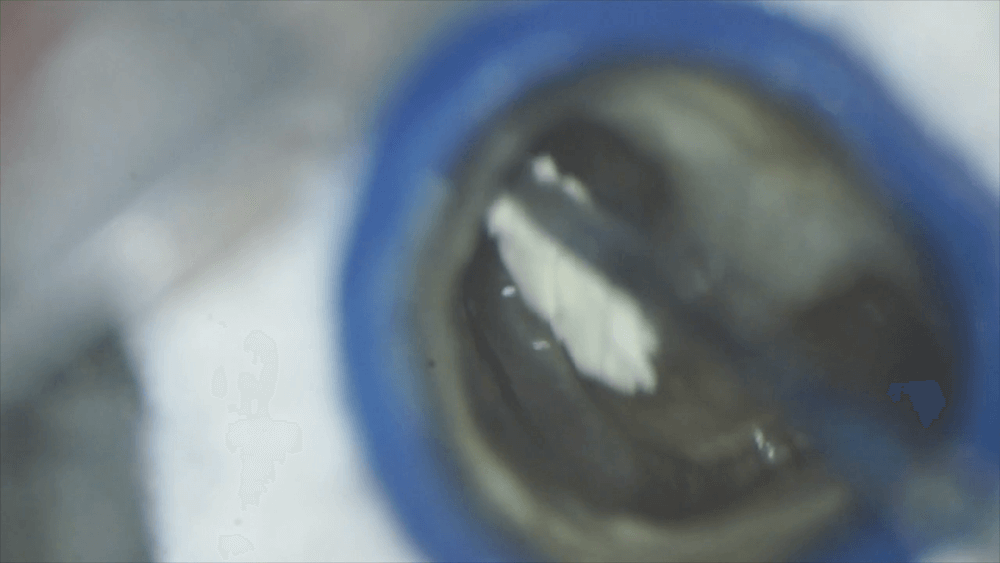

ラバーダムをして、仮封を取り除き、根の内部をよく洗浄し、根管充填を行いました。

まずは遠心根をMTAセメントで根管充填します。

根尖の方まで充填します。

このMTAセメントで、上の方まで敷き詰めます。